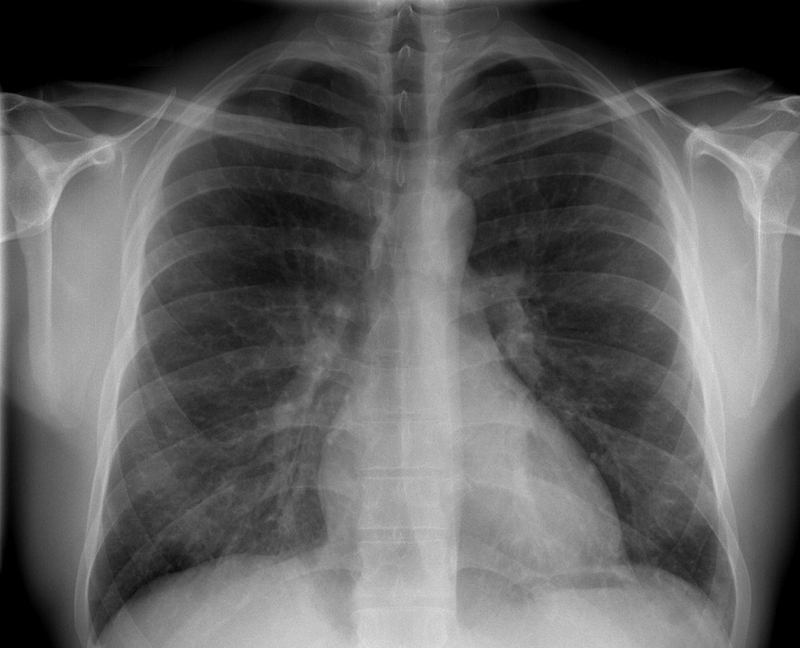

• Xét nghiệm hình ảnh học như chụp X-quang ngực, CT ngực, nội soi phế quản, hút dịch phế quản: Kết quả chụp X-quang ngực hiển thị có đám mờ di chuyển khác so với vị trí trước đó từ 12 đến 20 ngày. Tuy vậy, những tổn thương phổi quan sát thấy trên phim chụp có thể sẽ hoàn toàn biến mất trong 2 - 4 tuần. Khi mắc bệnh tăng bạch cầu ái toan ở phổi do thuốc, những bất thường trên phim X quang sẽ biến mất hoàn toàn trong vài tuần sau khi dừng việc dùng thuốc nghi ngờ gây bệnh.

Hội chứng Loeffler: Triệu chứng, cách chẩn đoán và điều trị bệnh 3 Chẩn đoán hình ảnh giúp chẩn đoán Loeffler